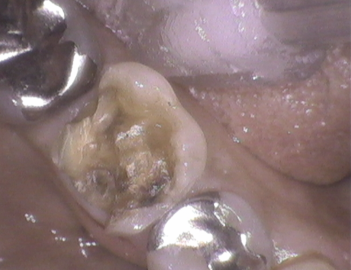

金属が外れて来院。金属、樹脂等の詰め物の選択はありましたが、1日で治療を完了したい旨に添い、レジン充填。

ちょっと体積は大きかったです。隣接歯とのコンタクトをしっかりとり、噛み合わせを確認。レジン充填ですから、咬耗が今後生じます。管理していきましょう。